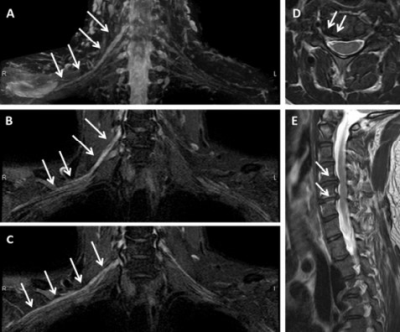

Figure 3. MRN examination of brachial plexus in cervical spondylotic radiculopathy. (A, B, C) coronal T2-TDEAL images; (D) Axial T2WI showed that the right intervertebral foramen of C4/5 intervertebral disc protruded; (E) T2WI sagittal position; The signal of right C5 and C6 nerve roots and corresponding segments of brachial plexus was significantly higher than that of left side (long arrow A, B, C). At right C4/5 and C5/6, herniation of intervertebral disc and stenosis of corresponding intervertebral foramen can be seen (short arrows D, E).